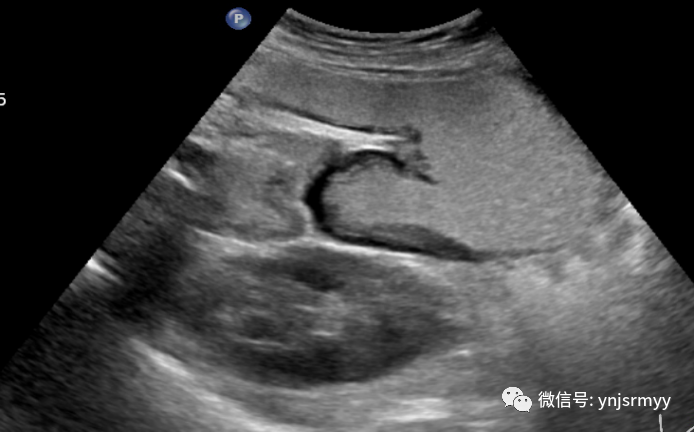

异位胰腺

什么是260胃镜胃肠不适,不想做胃镜,建水县人民医院胃肠超声造影检查能看!_https://www.jmylbn.com_新闻资讯_第6张